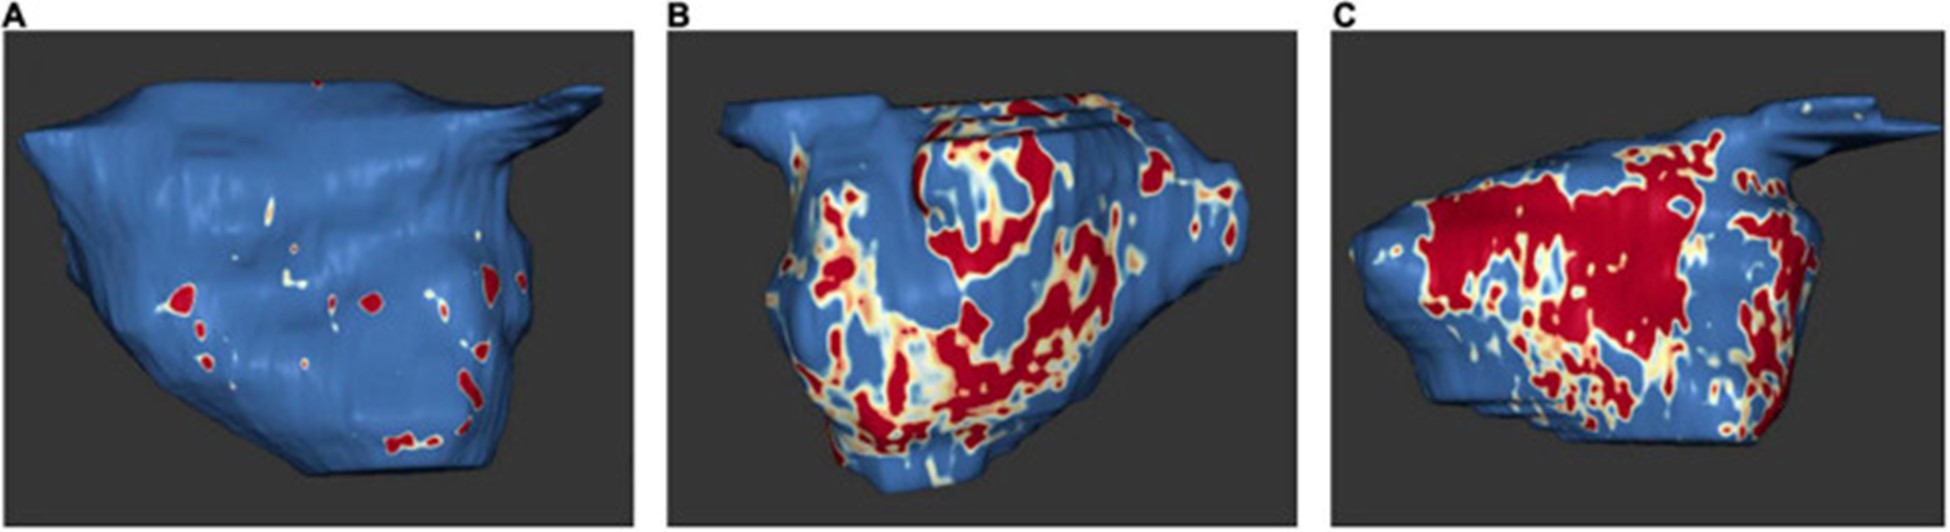

延迟增强磁共振成像

近年来,延迟增强MRI成为检测心房纤维化的关键方法。旨在通过病理延迟增强 MRI 定义左心房心肌病的研究特别关注临床定义(例如 AF、缺血性卒中、主要不良心血管事件)以及进一步的影像学定义(例如异常超声心动图参数、电解剖标测中的低电压区域) (表格1)。

2009 年,Oakes 等人。建立了犹他阶段模型来量化 LA 纤维化 。根据该模型,将严重程度分为四个级别:犹他州 I,定义为 ≤ 5% LA 壁增强,犹他州 II,5–20%,犹他州 III,20–35%,犹他州 IV,>35% (图 5)。

图 5:左心房 MRI 检查示例:基于 3D 延迟增强磁共振成像扫描的左心房组织纤维化。正常左心房壁以蓝色显示,纤维化改变以红色和白色显示。纤维化量占左心房壁总体积的百分比。(A)犹他州第一阶段 (1%)。(B)犹他州第 3 阶段 (27%)。(C)犹他州第 4 阶段 (36%)。在 Misagh Piran 博士(Herz- und Diabeteszentrum Nordrhein-Westfalen,Ruhr-Universität Bochum)的友好支持下。

延迟增强 MRI 与来自 LA 结构重塑的手术活检组织学之间发现了高度相关性,包括间质和脂肪纤维化以及总纤维化和脂肪 。原生 T1 对应于 MRI 和组织学的纤维化程度 。此外,与没有 AF 的患者相比,AF 患者的 LA 壁增强似乎更大(77)。

延迟增强 MRI 发现的 LA 瘢痕区域与心内膜标测中的低电压区域有关 。

由于 LA 晚期钆增强与 LA 射血分数和超声心动图左室间隔 e' 和室间隔 E/e' 之间存在显着相关性,因此更高量的 LA 晚期钆增强与 LA 功能下降以及 LV 舒张功能下降有关(79)。斑点追踪超声心动图也证明了延迟增强和 LA 功能降低之间的相关性。延迟增强 MRI 测量的 LA 壁纤维化程度与斑点追踪超声心动图显示的 LA 应变和应变率之间存在反比效应,特别是 LA 中外侧应变和应变率(80)。有趣的是,与阵发性 AF 患者相比,持续性 AF 患者出现更多的纤维化和更少的中间隔和中外侧应变 。一般来说,新发房性心律失常的风险随着 LA 晚期钆增强量的增加而增加 。

既往卒中患者和卒中高危患者(表现为 CHA2DS2-VASc 评分高)在延迟增强 MRI 中 LA 纤维化的比例显着增加。LA 纤维化是脑血管事件的独立预测因子,显着提高了 CHA2DS2-VASc 评分的预测能力 。上升的犹他阶段和更强烈的 LA 晚期钆增强与主要心血管事件的风险增加有关,主要是由于中风或 TIA 的风险增加(82)。有趣的是,与 AF 患者相比,ESUS 患者的心房纤维化程度相似,这支持了纤维化是缺血性卒中和左心房心肌病的主要危险因素的假设(83)。

通过延迟增强 MRI 测量的结构性 LA 重塑程度似乎与 AF 类型(孤立性 AF 或非孤立性 AF)无关(84)。已证明 AF 消融后的结果显着取决于结构性 LA 重塑的程度,在犹他州分期增加时结果更差 。随着延迟增强水平的增加,消融后 AF 复发的发生频率更高(75)。因此,通过延迟增强 MRI 进行的消融前 LA 纤维化评估可以预测结果 。另一项研究 LA 纤维化对 AF 消融后结果的影响的研究表明,延迟增强 MRI 检测到的 LA 纤维化等级较高时,复发性心律失常的风险出现。77 )。较高的 LA 纤维化等级的存在也是成功消融的最佳预测指标,而增加的 LA 体积和持续性 AF 没有预测作用 。